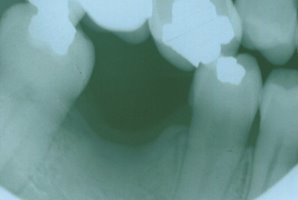

Orthodontics To Upright A Severely Tilted Molar

This patient had lost his first molar and the molar behind it collapsed

into the residual space. This was not a situation that was conducive to

placing a fixed bridge because of the misalignment. By performing a

simple, minor orthodontic procedure, the tooth was uprighted into its

original position and replaced with a beautiful fixed bridge. Now this

patient is able to chew his food properly, and lessen his chances of TMJ

(jaw joint) problems. |